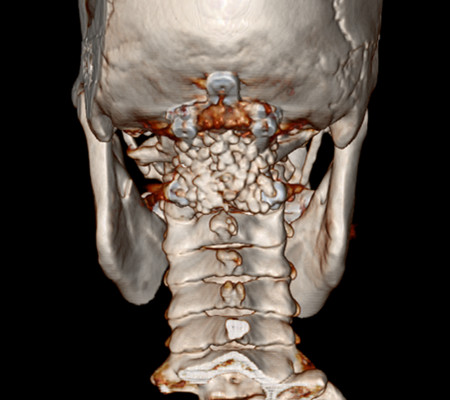

患者,女,53歲,以“頸肩部麻木、疼痛10月”入住神經(jīng)外科一病區(qū)。該患者小腦扁桃體下疝畸形,頸椎先天發(fā)育也有異常。

主任劉增強(qiáng)、責(zé)任總醫(yī)師巨濤等人就此病例進(jìn)行了多次討論。術(shù)前第一次運(yùn)用先進(jìn)的3D打印技術(shù)重塑了患者的寰枕部骨質(zhì)及血管,證實(shí)了患者先天性寰椎后弓缺如。經(jīng)過充分的術(shù)前準(zhǔn)備,顯微鏡下切除了下疝的小腦扁桃體,結(jié)合3D打印結(jié)果,歷時4小時完成了我院第一例后路減壓+枕頸內(nèi)固定術(shù)?;颊咝g(shù)后3天下床活動,10天出院。

寰枕畸形是指枕骨底部及第一、二頸椎先天發(fā)育異常,除以骨骼為主的發(fā)育異常外,還合并有神經(jīng)系統(tǒng)和軟組織發(fā)育異常,包括扁平顱底、顱底陷入、寰枕融合、頸椎分節(jié)不全、寰樞椎脫位、小腦扁桃體下疝畸形等。